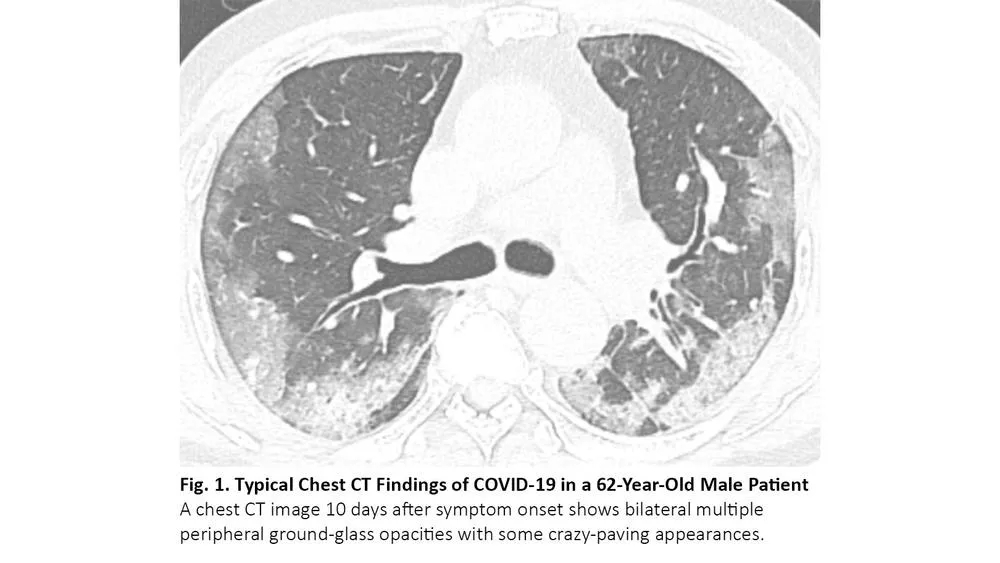

肺癌患者在病程中可能出现与COVID-19类似的CT异常,但这些异常是由于其他原因,如病毒性肺炎、癌症复发和间质性肺病。病毒性肺炎,特别是流感肺炎,在胸部CT上可表现为双侧磨玻璃样影和实性病变,胸部CT上位置分布相似10(图3),秋冬流感高发时,利用放射学检查结果来鉴别二者可能有问题。COVID-19 CT比流感肺炎CT更多见小叶间隔增厚及圆形阴影(典型肺周分布),但肺结节和树芽征相对更少。11

图3. 流感肺炎